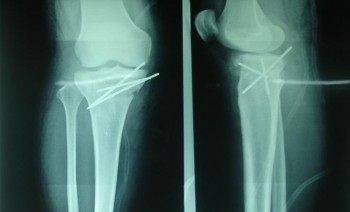

• Gãy hở độ IIIC hoặc gãy hở thân xương đùi, thân xương chày đến muộn sau 6 giờ; gãy 1/3 dưới thân xương đùi hoặc xương chày: cố định ngoài bằng khung F.E.S.S.A (ảnh 2.1) hoặc cọc ép ren ngược chiều;

• Gẫy đầu dưới xương đùi, gẫy mâm chày: kết hợp xương bằng đinh Kirschner (ảnh 2.2) hoặc bắt vít xương xốp;

Ảnh: 2.1: Hình ảnh kết hợp xương chày bằng khung F.E.S.S.A.

(Bệnh nhân Lưu Trung Đ., 20 tuổi. Số BALT :366)